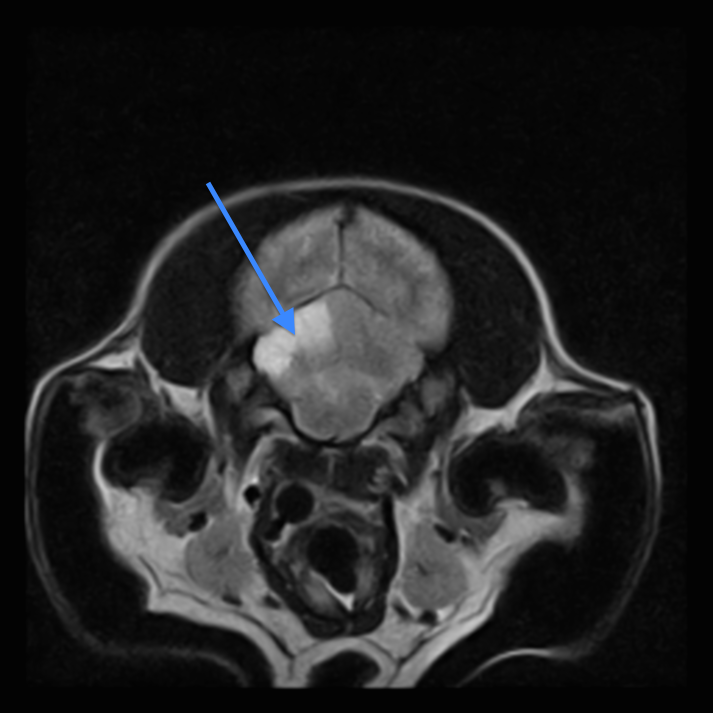

Det afficerede område påvirkes forskelligt afhængigt af graden af iskæmi og kan på den baggrund inddeles i to zoner: Kernen og penumbraen12 (figur 1). I kernen af det iskæmiske område forekommer den alvorligste hypoperfusion med irreversibel infarktdannelse og vævsdød til følge12. Penumbraen betegner derimod det område, der omgiver kernen, og hvor hypoperfusionen er mindre udtalt, og celledød derfor endnu ikke er indtrådt12. Her er der reelt mulighed for rekonvalescens af det afficerede vævsområde, såfremt en tilstrækkelig blodforsyning kan genetableres inden for et kortere tidsrum, typisk op til 6-8 timer. Denne tilstand kan derfor være reversibel ved korrekt terapeutisk intervention13. Hvis ikke perfusionen genoprettes, vil penumbraen gradvist omdannes til et irreversibelt infarkt11.

Figur 1 Apopleksi

Figur 1. MR-billede (T2-vægtning, tværsnit) af akut MCA-infarkt i hundehjerne med skematisk illustration af den iskæmiske penumbra og infarktets kerne. Kernen defineres som det område af infarktet, hvor der er sket irreversible skader som følge af alvorlig hypoperfusion. Infaktkernen omgives af penumbraen, som betegner det område, hvor hypoperfusionen er mindre udtalt, og celledød endnu ikke er indtrådt, og skaderne derfor er potentielt reversible.